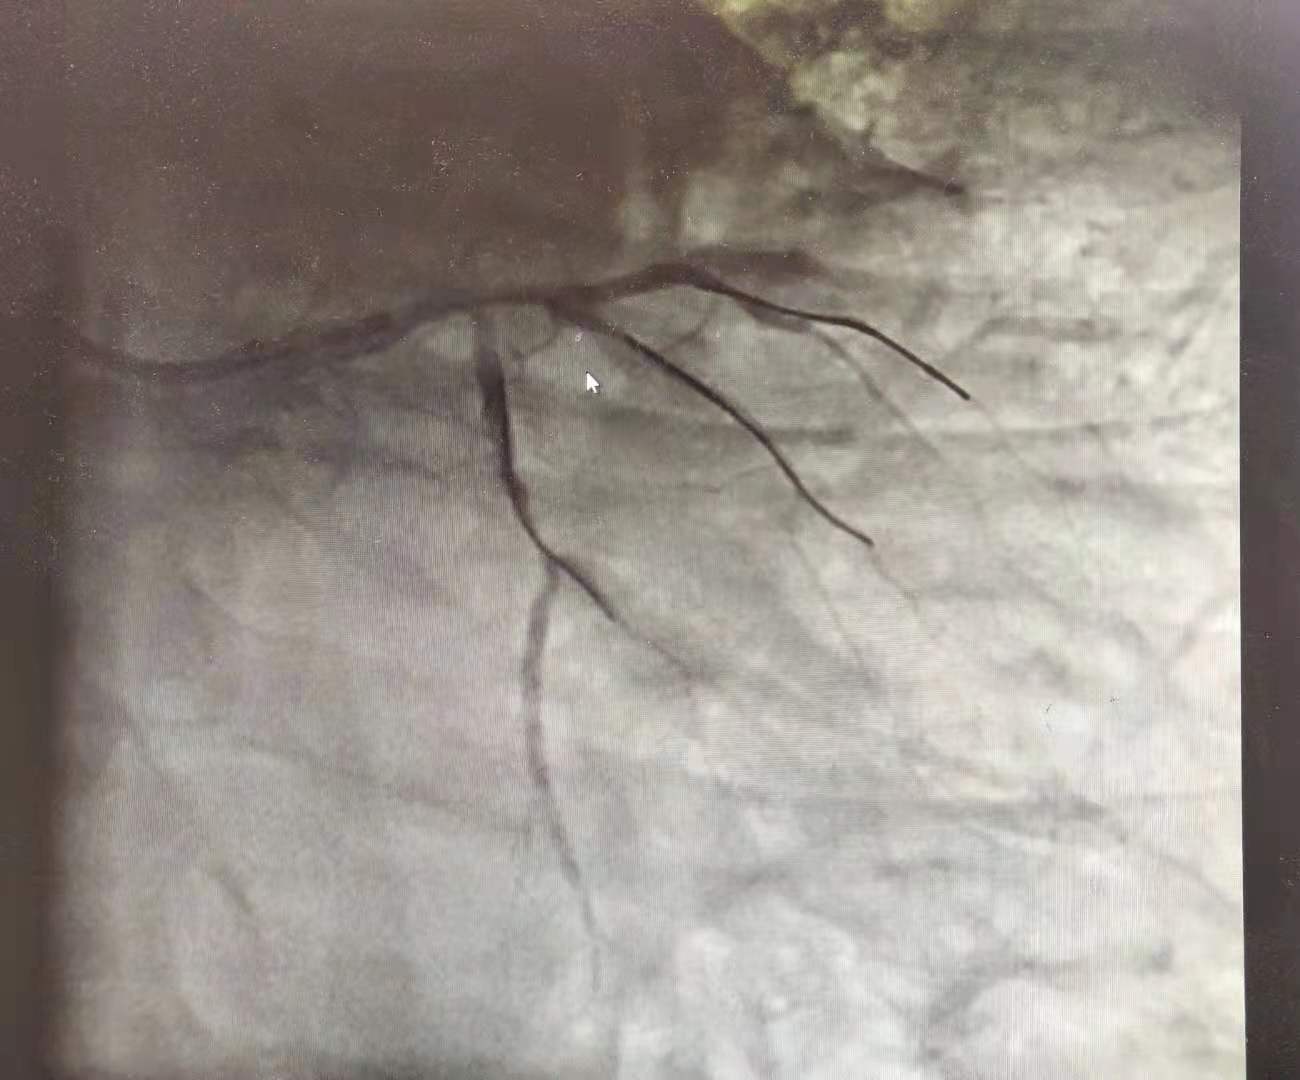

我通知手术室提前做好准备,立即护送患者手术。由于患者严重的低血压状态,我们率先植入了心脏辅助装置(IABP)帮助心脏跳动,降低术中猝死的风险。然后迅速进行冠状动脉造影……

我的疑惑解开了,但是后背也立刻泛起一股凉意:左侧的3根主要心脏血管(前降支、中间支、回旋支),只剩下1根回旋支!而这根血管开口也能看到血栓、接近堵死!

回想心电图表现,我们确定:此次急性心梗是由于中间支新发堵塞造成;而患者以前确实得过大面积心肌梗死,那根闭塞的前降支就是证明!原来患者2年来饱饭后反复出现“上腹痛”根本不是胃病,而是被“误诊”的心绞痛甚至心肌梗死!

我们一边叫来ICU准备气管插管,以防不测,一边手术继续。经过各种导丝、球囊的精细操作,以及血栓抽吸,我们终于开通这次的“犯罪血管”——中间支;而另一根血管堵塞的时间太长,根本无法开通,过多纠缠只会增加猝死风险。我们认为可以结束手术,先将病人转入ICU,再谨慎决定下一步方案。